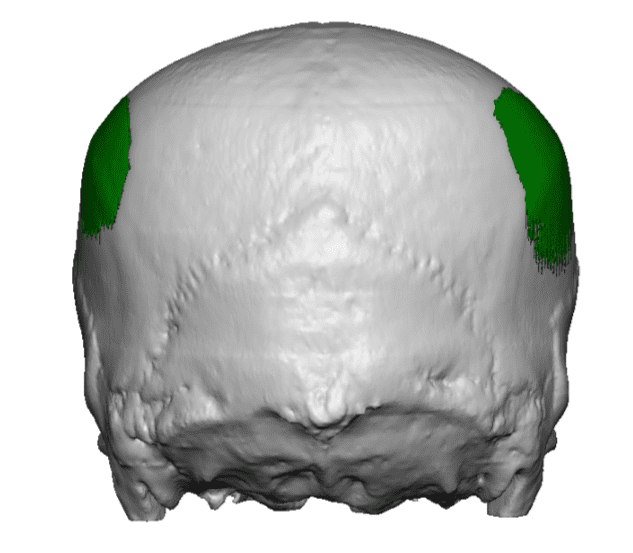

Desire for head shape asymmetry improvement as the final stage of total skull reshaping surgeries. (previous skull implants are in green color)

Placement of custom temporal implant through an incision behind the ear.

Desire for head shape asymmetry improvement as the final stage of total skull reshaping surgeries. (previous skull implants are in green color)

Placement of custom temporal implant through an incision behind the ear.